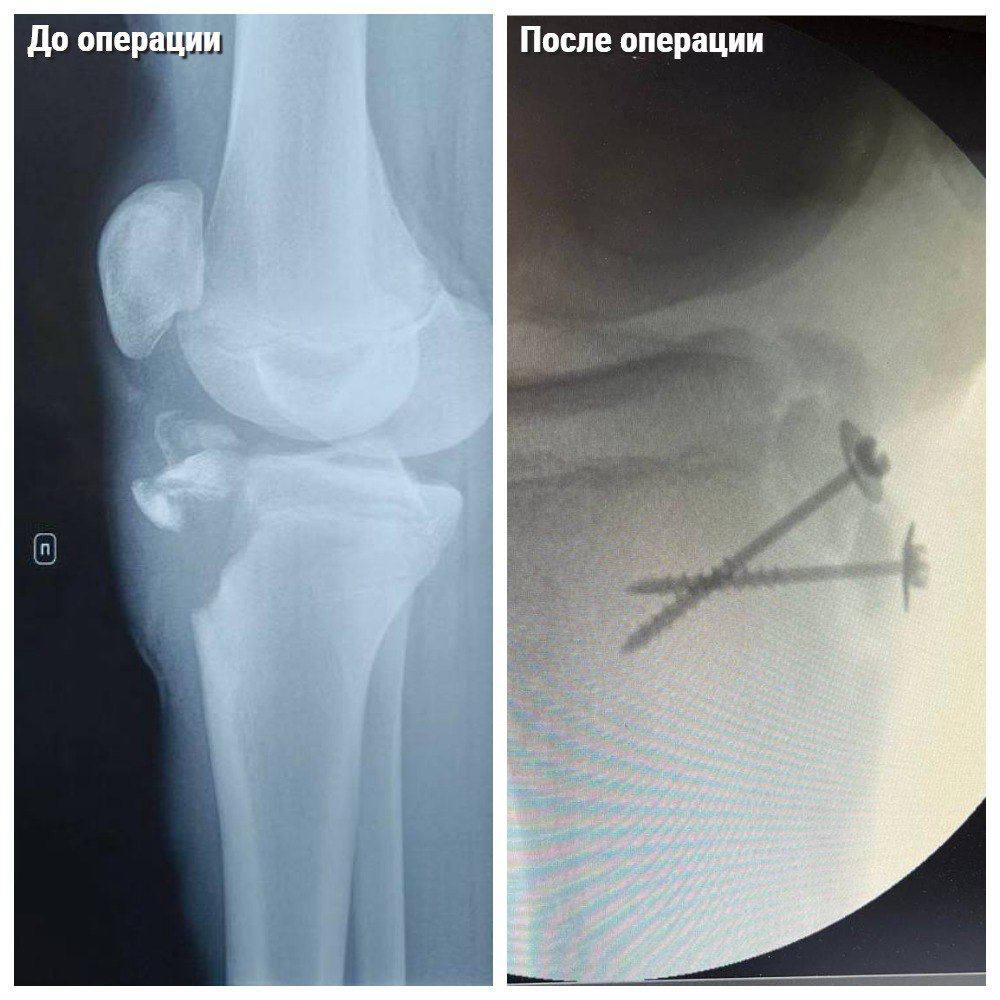

В Московскую областную детскую травматолого-ортопедическую больницу поступил 15-летний пациент с жалобами на сильную боль в колене. Как выяснилось, у него оторвался фрагмент большеберцовой кости во время тренировки по баскетболу — парень хотел научиться выше подпрыгивать до кольца, но пренебрег разминкой и травмировался.

«Отрыв бугристости большеберцовой кости — это тяжелая травма, которая требует обязательного хирургического лечения для восстановления полноценного объёма движений нижней конечности. При проведении ревизии коленного сустава мы обнаружили многооскольчатый перелом. Отломки кости зафиксировали винтами, а связку подшили биодеградируемым, то есть рассасывающимся, швом», — рассказал заведующий травматолого-ортопедическим отделением №3 Сергей Катин.

Со спортом молодому человеку придется на время завязать — в будущем придется вынимать винты из ноги и долго реабилитироваться.